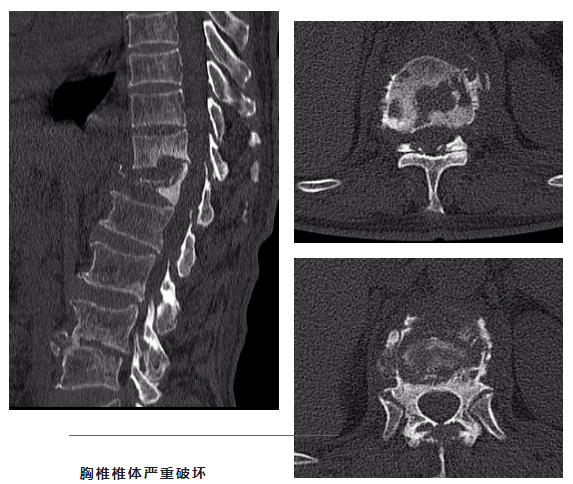

胸椎椎体严重破坏

结合相关检查诊断为胸11、12、腰3、4椎体结核、T12椎体破坏继发胸腰段后凸畸形。因患者未规律口服抗结核药物,胸腰部未制动,保守治疗无效,椎体破坏后继发胸腰段后凸畸形,出现肋间神经损伤症状,且胸12椎体骨质破坏严重,随时有椎体破坏加重后凸至瘫痪的可能,骨科团队经过详细讨论建议手术治疗。